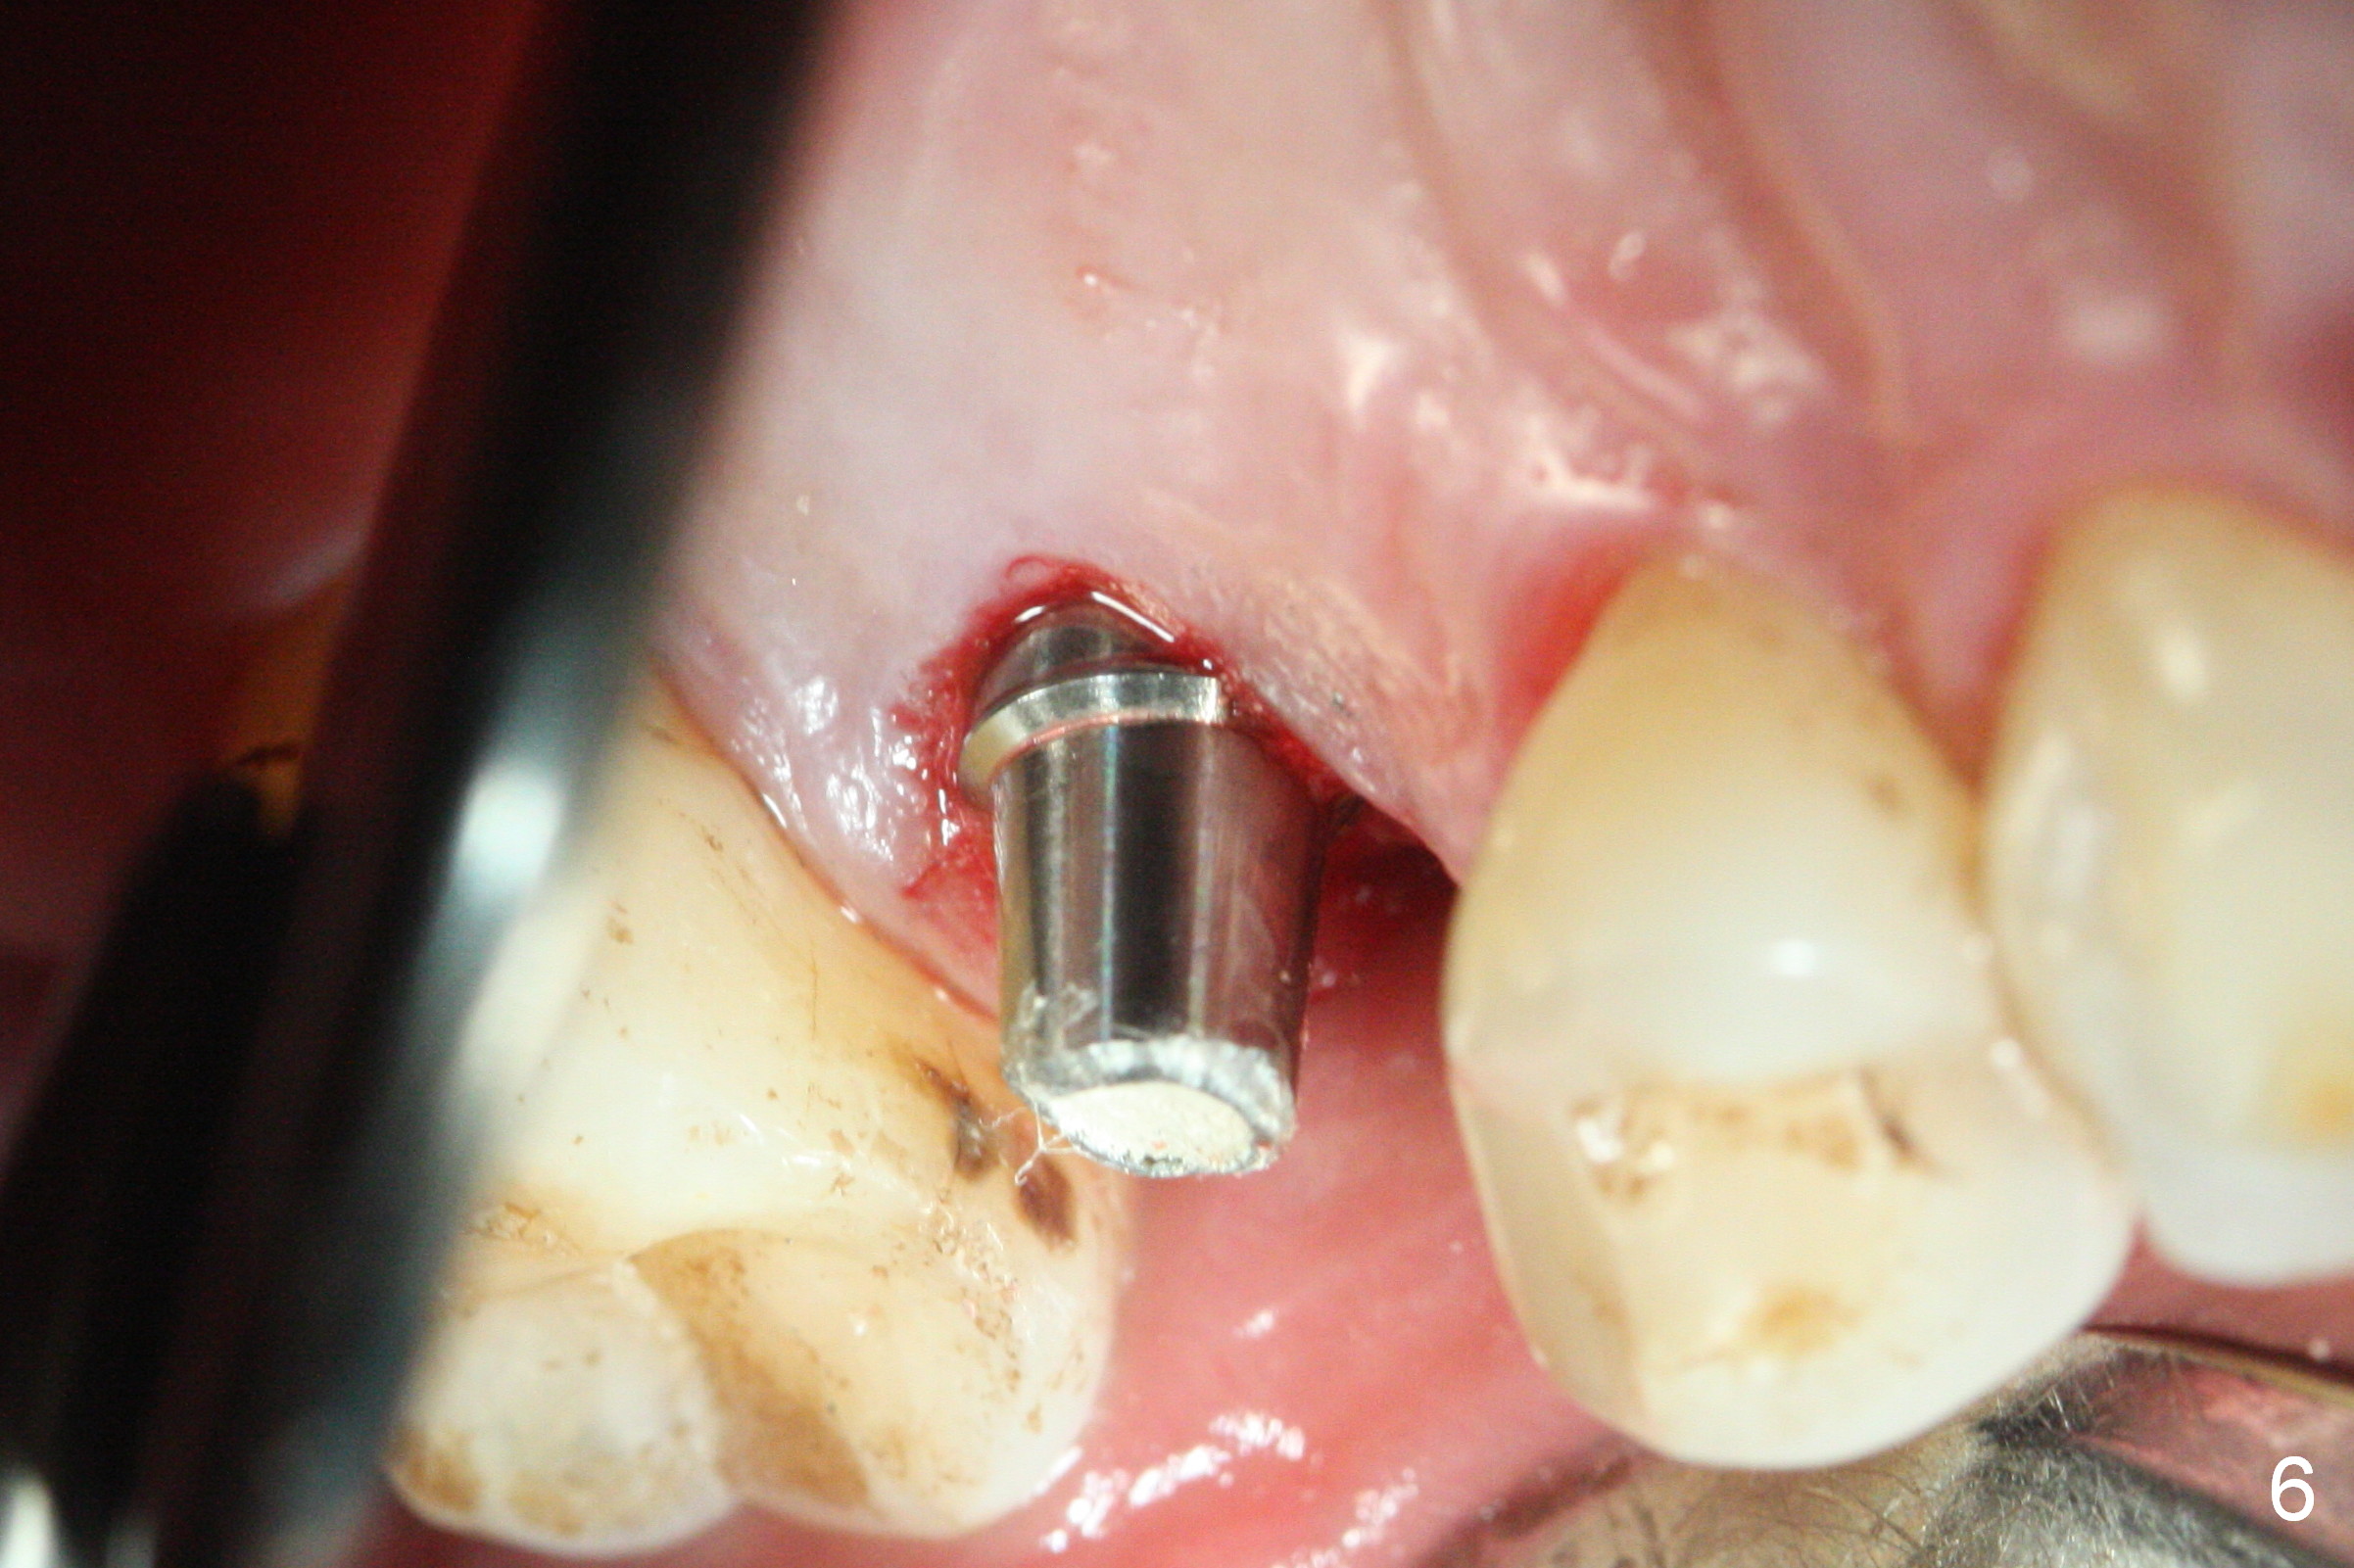

Initial osteotomy depth is 18 mm (Fig.1 green line) with 9 mm in the native bone (red line).  The bone density feels to be low.  There is at least 2 more mm bone apically (pink line).  The depth is increased by 2 mm so that when a 3.8x15 mm implant is placed, there is 10-11 mm implant/bone contact (Fig.2 red line).  There is large bony defect (Fig.3 *), which is bone grafted (Fig.4 *).  Finally a longer abutment is placed (4.5x5.5(5) in Fig.4 vs. 4.5x4(5) in Fig.2,3).  The 5 mm cuff does not look too long buccally (Fig.5) or palatally (Fig.6).   To prevent postop buccal gingival overgrowth (2), the buccal margin of an immediate provisional is subgingival (Fig.7-9 *).  Bone density between #13 and 14 appears to increase 3 months postop (Fig.10).  The implant seems to be equi-crestal (Fig.11 ^).  There seems to be more bone growth (i.e., decreasing gap) 6 months postop (Fig.12).  Impression is taken.  A crown is delivered nearly 7 months postop (08/07/2017).   While there is minimal bone loss at #13 and 15 three years and 4 months post cementation, the tooth #14 and 18 are mobile (Fig.13,14).